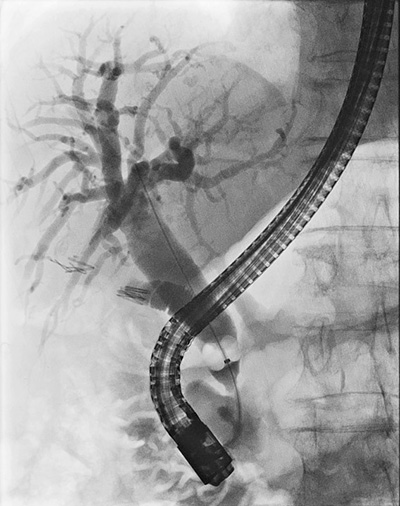

Endoskopisk retrograd kolangiopankreatografi (ERCP) på en patient som genomgått kolecystektomi. Bilden visar en omfattande

vidgning av gallvägarna.